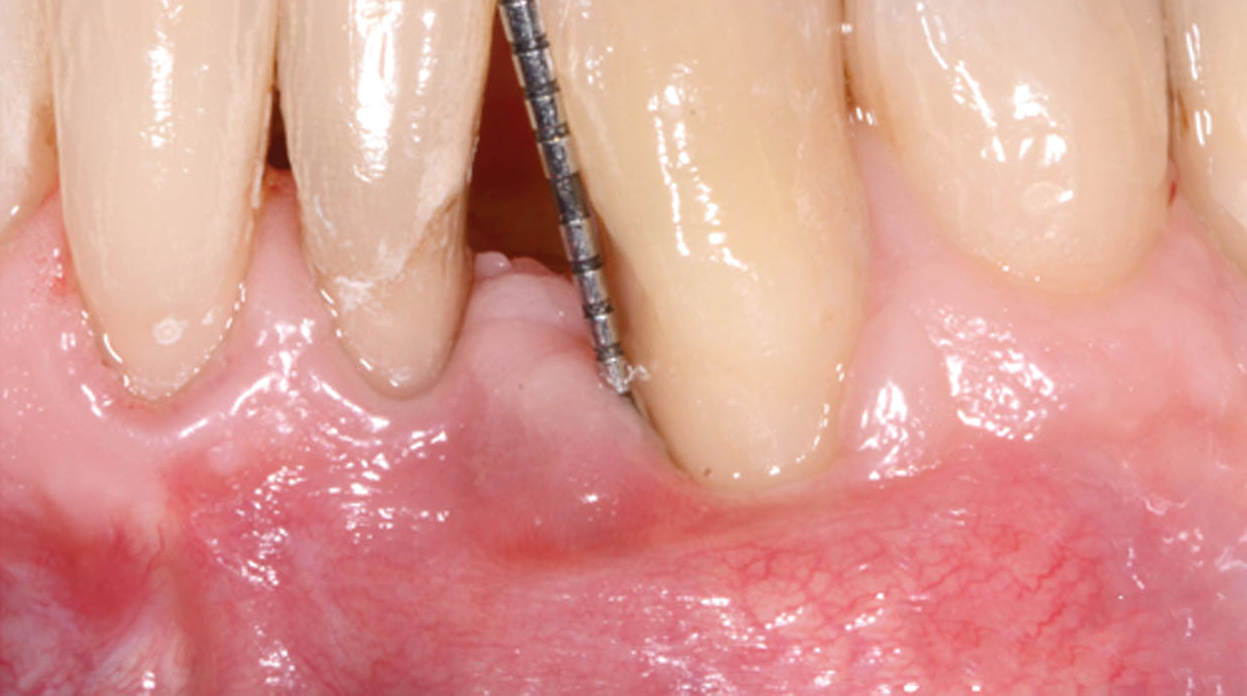

Fig 13. The scaffold was placed in the defect, where it remained for approximately 1 year. Fig 13: baseline; Fig 14: defect; Fig 15: scaffold matrix; Fig 16: scaffold placement; Fig 17: wound closure; Fig 18 through Fig 20: 2-month, 6-month, and 1-year postoperative, respectively. (Images reprinted with permission from Rasperini G, Pilipchuk SP, Flanagan CL, et al. J Dent Res. 2015;94[9 suppl]:153S-157S.)

Figure 13

Fig 14. The scaffold was placed in the defect, where it remained for approximately 1 year. Fig 13: baseline; Fig 14: defect; Fig 15: scaffold matrix; Fig 16: scaffold placement; Fig 17: wound closure; Fig 18 through Fig 20: 2-month, 6-month, and 1-year postoperative, respectively. (Images reprinted with permission from Rasperini G, Pilipchuk SP, Flanagan CL, et al. J Dent Res. 2015;94[9 suppl]:153S-157S.)